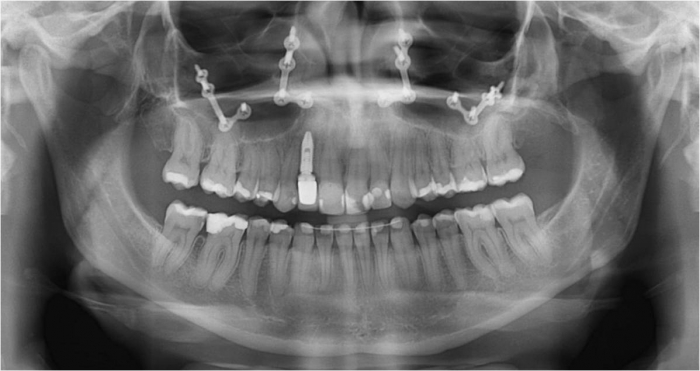

Raio X inicial - Clínica Cliniface

Raio X inicial